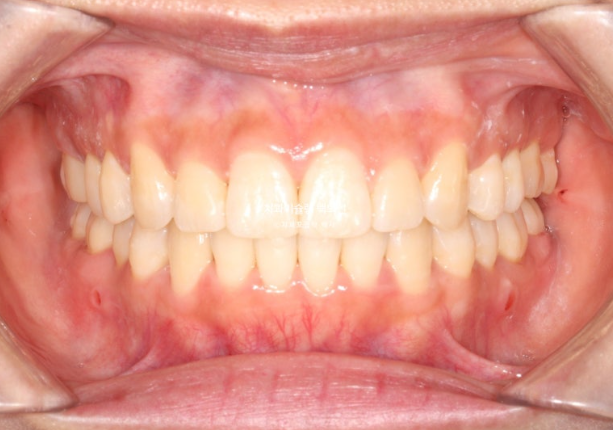

25년 5월부터 8월까지 14개 추가장치를 모두 낀 후 치료를 마무리 했습니다.

25.08

중심선은 일치하고 교합도 좋습니다.

파란화살표 둘째 큰어금니 (제2대구치)자리에 있는 치아는 사실 사랑니입니다.

그 앞 제 1대구치 자리에 와있는 치아는 사실은 제 2대구치입니다.

이제 전후비교 보겠습니다.

총 치료기간은 1년 10개월, 재제작은 2회 했습니다.

23.10~25.08

발치된 큰어금니 자리를 뒤에있는 제2대구치와 사랑니로 감쪽같이 대체되었습니다.